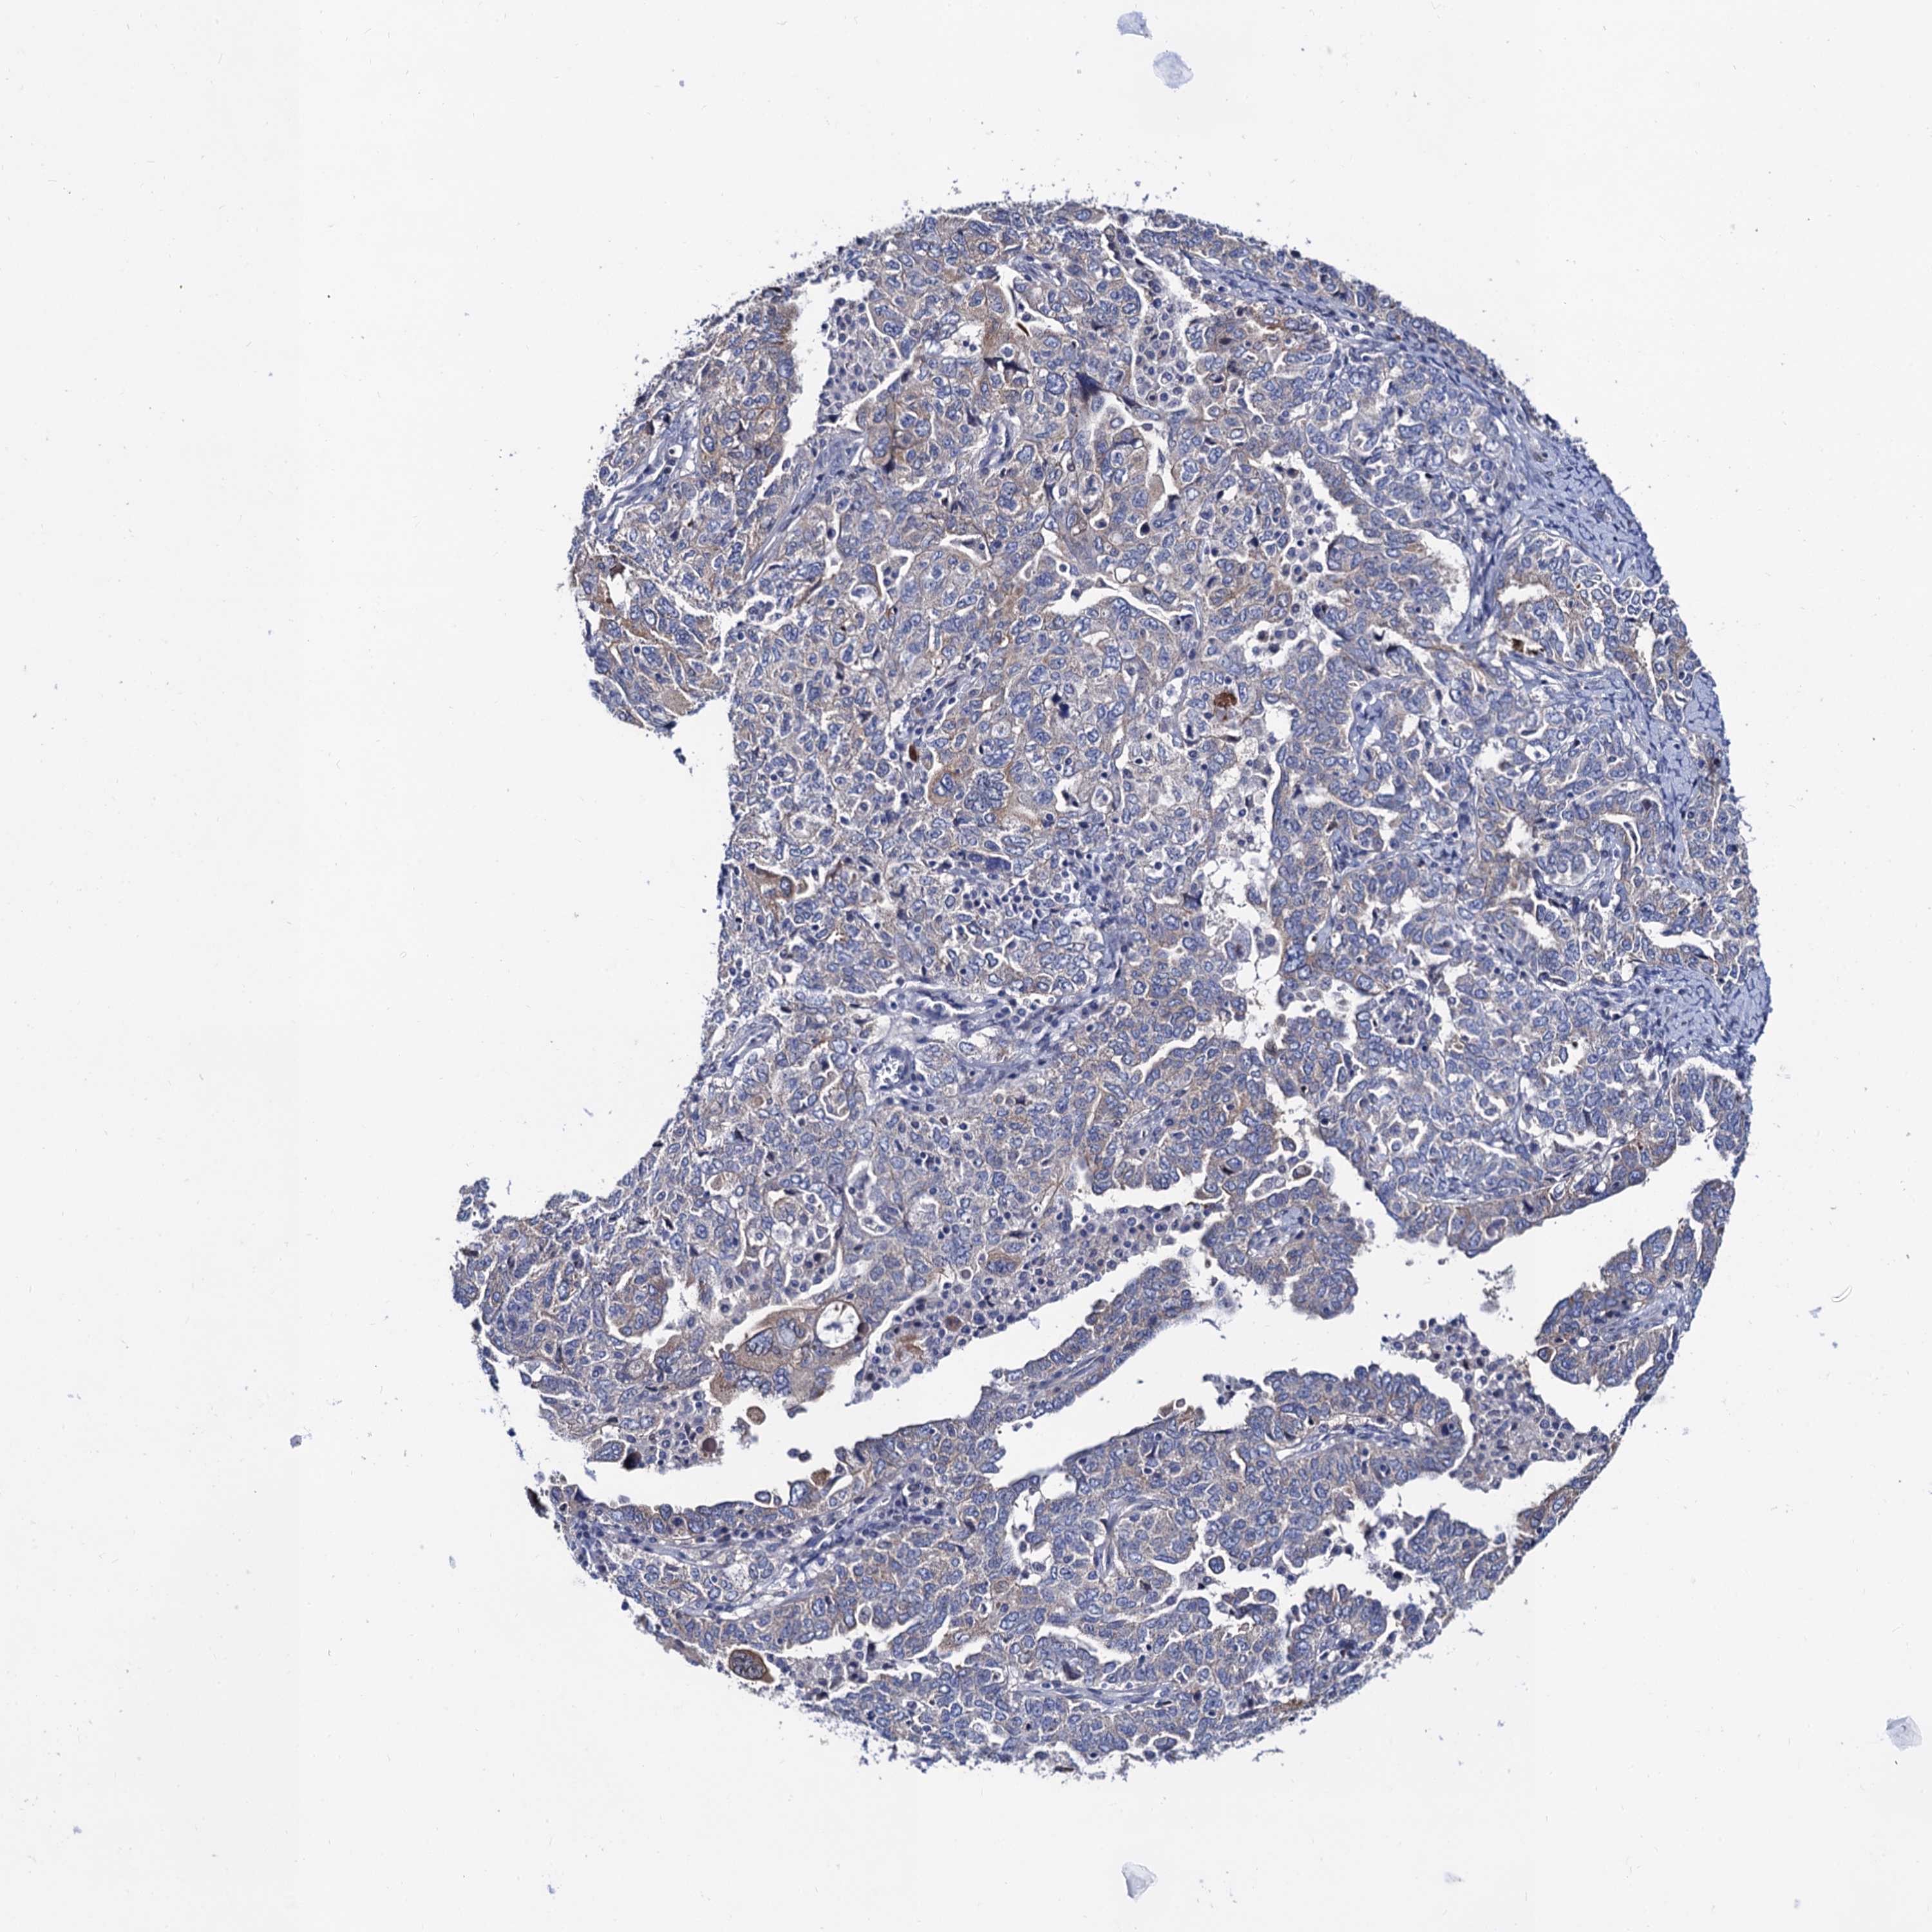

OVARIAN CANCER - Protein expressioni

A mouse-over function shows sample information and annotation data. Click on an image to view it in a full screen mode. Samples can be filtered based on level of antibody staining by selecting one or several of the following categories: high, medium, low and not detected. The assay and annotation is described here.

Note that samples used for immunohistochemistry by the Human Protein Atlas do not correspond to samples in the TCGA dataset.

Antibody stainingi

Antibody staining in the annotated cell types in the current human tissue is reported as not detected, low, medium, or high, based on conventional immunohistochemistry profiling in selected tissues. This score is based on the combination of the staining intensity and fraction of stained cells.

Each image is clickable and will lead to virtual microscopy that enables deeper exploration of all samples and also displays staining intensity scores, fraction scores and subcellular localization as well as patient and tissue information for each sample.

Antibody HPA040234

Staining

High

Medium

Low

Not detected

Intensity

Strong

Moderate

Weak

Negative

Quantity

>75%

75%-25%

<25%

None

Location

Nuclear

Cytoplasmic/membranous

Cytoplasmic/membranous,nuclear

Cystadenocarcinoma, serous, NOS

Carcinoma, endometroid

Cystadenocarcinoma, mucinous, NOS

Carcinoma, NOS